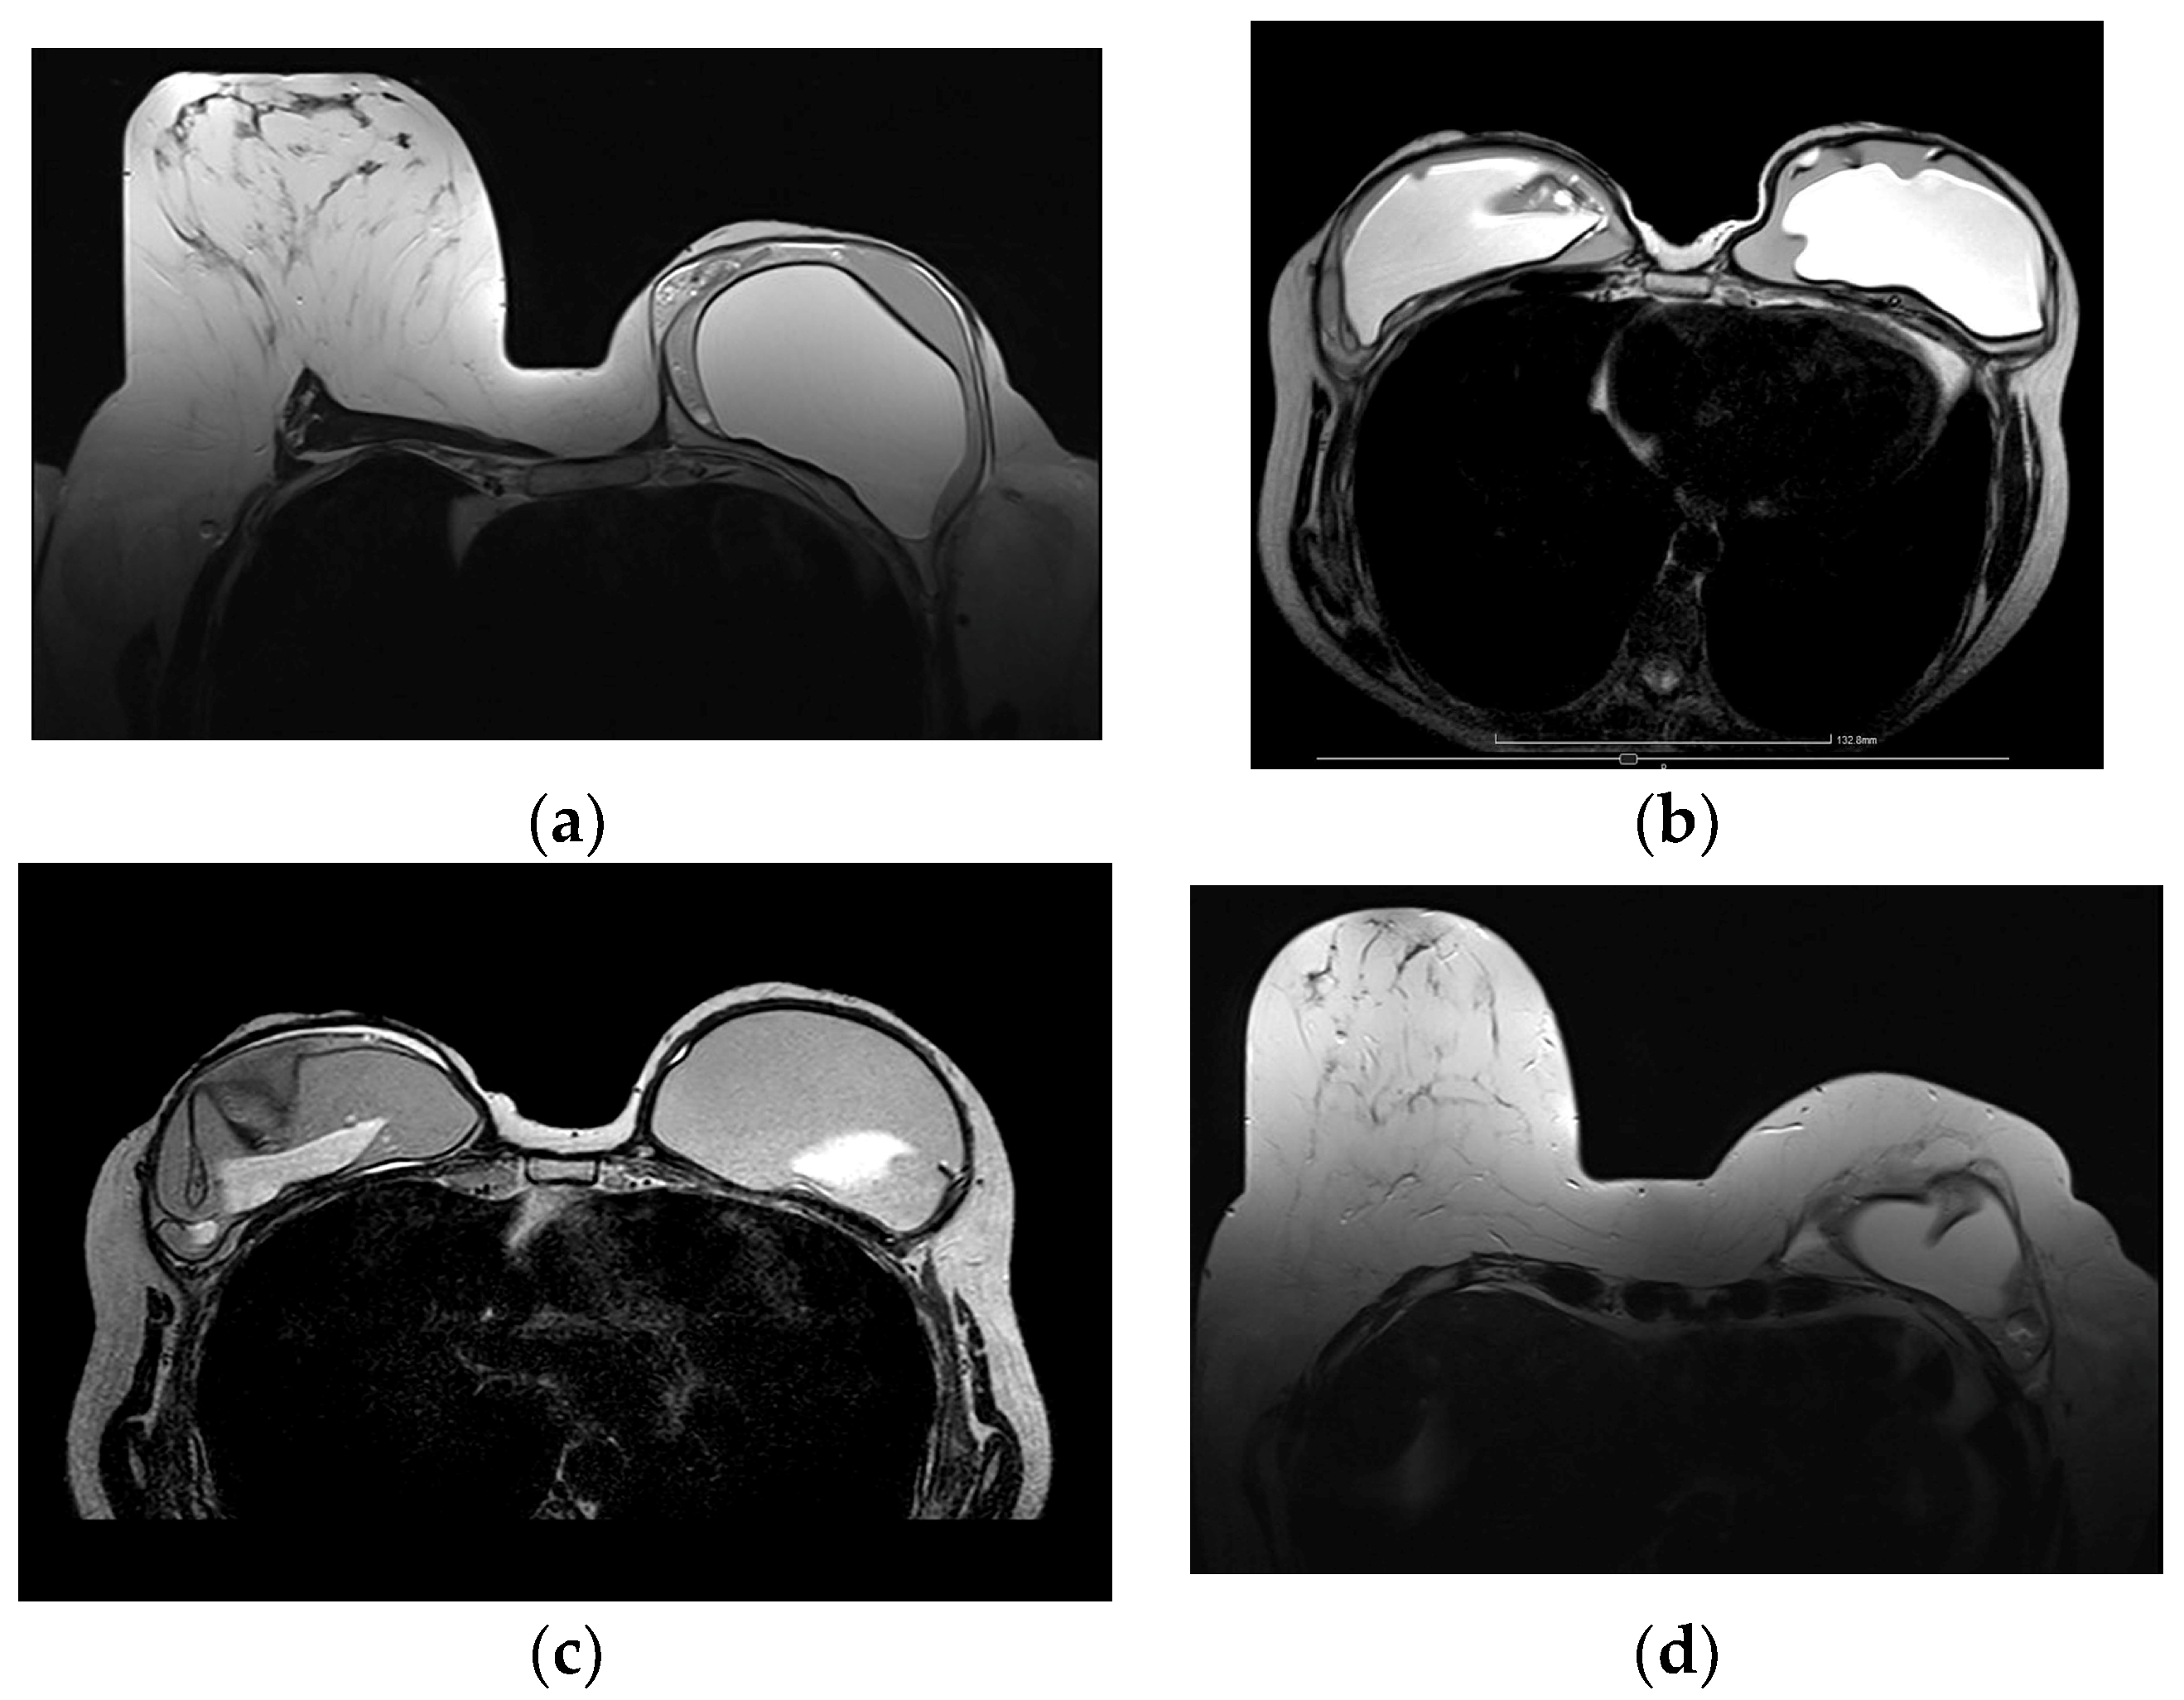

5.2.5. Implant Rupture

5.2.6. Breast Implant Associated Atypical Large Cell Lymphoma (BIA-ALCL)

- Sharma, B.; Jurgensen-Rauch, A.; Pace, E.; Attygalle, A.D.; Sharma, R.; Bommier, C.; Wotherspoon, A.C.; Sharma, S.; Iyengar, S.; El-Sharkawi, D. Breast Implant-associated Anaplastic Large Cell Lymphoma: Review and Multiparametric Imaging Paradigms. Radiographics 2020, 40, 609–628. [Google Scholar] [CrossRef] [PubMed]

- Adrada, B.E.; Miranda, R.N.; Rauch, G.M.; Arribas, E.; Kanagal-Shamanna, R.; Clemens, M.W.; Fanale, M.; Haideri, N.; Mustafa, E.; Larrinaga, J.; et al. Breast implant-associated anaplastic large cell lymphoma: Sensitivity, specificity, and findings of imaging studies in 44 patients. Breast Cancer Res. Treat. 2014, 147, 1–14. [Google Scholar] [CrossRef] [PubMed]

- Rotili, A.; Ferrari, F.; Nicosia, L.; Pesapane, F.; Tabanelli, V.; Fiori, S.; Vanazzi, A.; Meneghetti, L.; Abbate, F.; Latronico, A.; et al. MRI features of breast implant-associated anaplastic large cell lymphoma. Br. J. Radiol. 2021, 94, 20210093. [Google Scholar] [CrossRef]

| Complications | Fluid | Early; low T1, high T2 | Seroma |

| Early; high T1, high T2 | Hematoma | ||

| Delayed, persistent (±mass) | BIA-ALCL, BIA-SCC | ||

| Thickened capsule | Irregular | Capsular contracture | |

| Enhancing with fluid | Infection | ||

| Mass | Cyst, complex cystic | Fat necrosis | |

| Fibrous capsule related | BIA-ALCL, BIA-SCC, desmoid, granuloma | ||

| Skin, subcutaneous | Fat necrosis, cancer recurrence, granuloma |